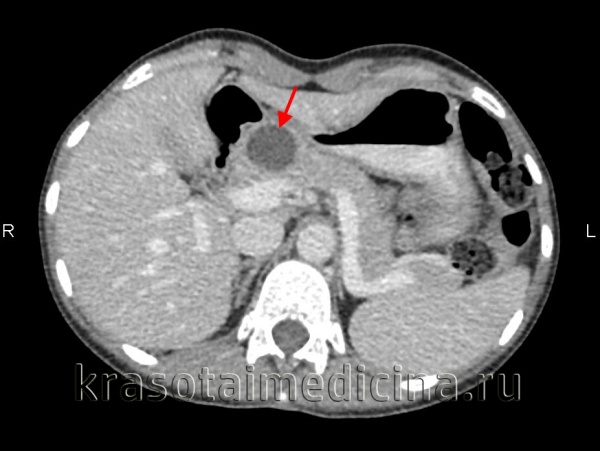

КТ органов брюшной полости. Диффузно увеличенная поджелудочная железа. Большая стрелка указывает на тело поджелудочной железы, маленькие стрелки - на абсцесс, расположенный в хвосте поджелудочной железы.